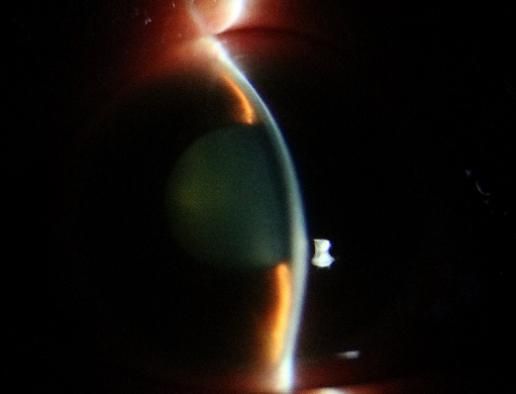

安徽省蚌埠市 60 岁的张阿姨在前往兰州的火车上突发右眼胀痛、视物模糊,还伴有头晕、恶心、呕吐等症状。休息后这些症状并未缓解,张阿姨在西安站下车后立即被送至我院急诊科就诊。急诊科医生考虑到症状可能与眼部疾病有关,遂请眼科医生会诊。经眼科医生仔细检查后发现,张阿姨右眼视力仅为指数,眼压高达 75 mmHg(正常眼压范围为 10-21 mmHg),角膜上皮弥漫性雾状水肿,前房极浅,瞳孔欠圆,直径约 6 mm,晶状体混浊。诊断为张阿姨是原发性急性闭角型青光眼,即右眼急性发作期、左眼临床前期,双眼老年性白内障。张阿姨随即被收住眼科病区,接受局部及全身降眼压药物治疗,效果不佳。考虑到持续高眼压对视神经的损伤,眼科范雅稚副主任当机立断为患者进行前房穿刺放液,眼压暂时得到有效控制。但经过一周的治疗及观察后,她的角膜始终未恢复透明,角膜内皮皱褶严重。

随后进一步的辅助检查发现张阿姨的眼部情况极为复杂,双眼小眼球的结构使得眼部的房水循环存在一定障碍,右眼前房深度仅 1.27 mm,左眼前房深度 1.67 mm,前房极浅的状况进一步阻碍了房水的正常流通,是引发眼压升高的重要因素之一。同时,张阿姨右眼还存在睫状体脱离的问题,这不仅影响了眼部的正常生理功能,还增加了治疗的难度。她的中央角膜处于灰白水肿状态,角膜不透明这一情况使得内路微创手术及白内障手术无法实施,医生难以清晰观察眼内结构,手术风险会大幅增加。如果不立刻手术,等待角膜恢复透明的过程中,患者又随时可能出现二次青光眼大发作的情况。